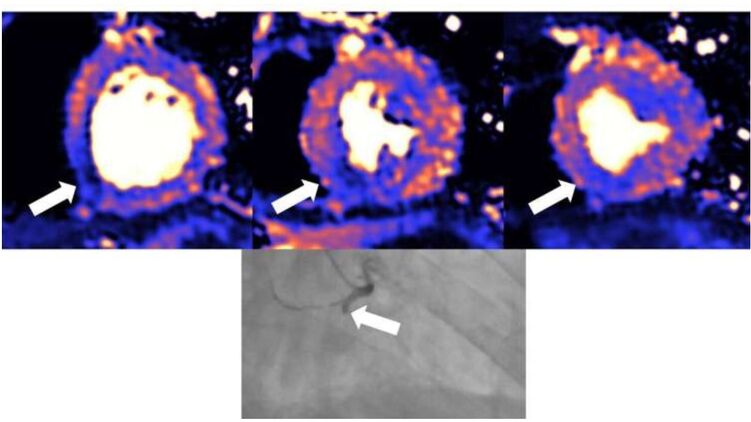

Оказалось, что у тяжелобольных пациентов очень часто наблюдались повреждения сердечной мышцы, которые можно было распознать на снимках спустя 1-2 месяца после выписки. При этом характер травм сердца был неодинаков, что указывает на то, что сердечно-сосудистая система подвержена различным типам воздействий со стороны вируса.

Функция левого желудочка, который отвечает за перекачку насыщенной кислородом крови ко всем частям тела, была нормальной у 89 процентов из 148 пациентов, хотя рубцы или другие повреждения сердечной мышцы присутствовали у 80 пациентов (54 %). Причиной появления рубцов и повреждений стало либо воспаление у 39 пациентов (26 %), либо ишемическая болезнь сердца у 32 пациентов (22 %), либо оба фактора у девяти пациентов (6 %). У 12 пациентов (8 %) воспалительные процессы все еще продолжались.